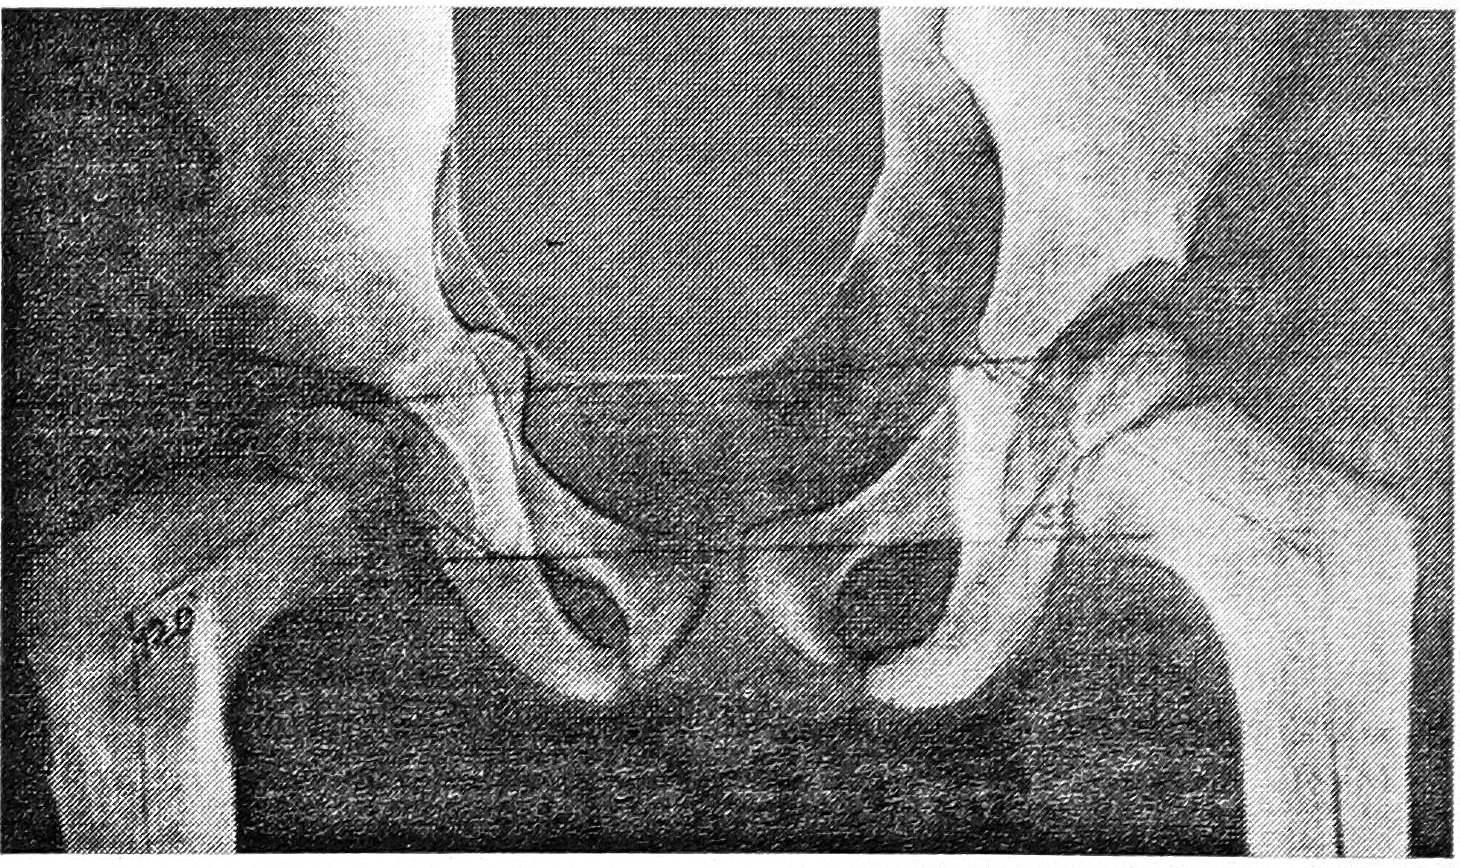

В 5 случаях (на первых этапах работы) мы приняли во внимание удовлетворительное значение ацетабулярного индекса по мягкотканным ориентирам. На операции также обнаружили хорошо развитый лимбус. После его расправления покрытие им головки было полным. В надежде на скорое обызвествление лимбуса и уменьшение ацетабулярного индекса выполнили только открытое вправление с деторсионно-варизирующей остеотомией бедра, без пластики крыши впадины. Однако в дальнейшем костная часть крыши впадины достаточного развития не получила (рис. 4). Ацетабулярный индекс оставался высоким, и постепенно нарастало уплощение впадины, возникал дефицит покрытия головки. В одном случае — вероятно, вследствие неправильного распределения биомеханических нагрузок из-за скошенности крыши впадины — возник рецидив вальгусной деформации шейки бедра. Из 5 рассматриваемых случаев удовлетворительный результат констатирован в 4.

Рис. 4. Больная Ц. 4,5 лет. Состояние после этапного открытого вправления врожденных вывихов бедер (патология была выражена примерно одинаково с обеих сторон). Слева — 2,5 года после открытого вправления вывиха с деторсионно-варизирующей остеотомией; справа — 1,5 года после открытого вправления вывиха с деторсионно-варизирующей остеотомией бедра и пластикой крыши впадины по Солтеру.